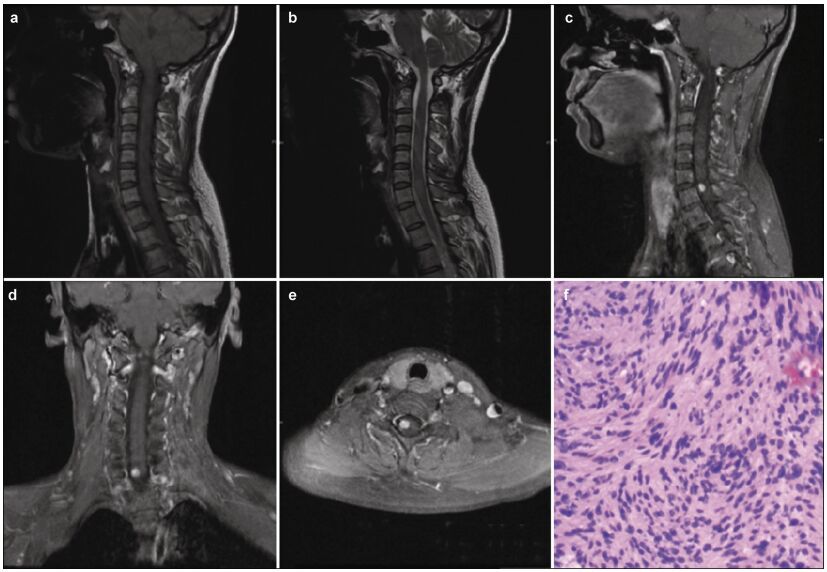

2 Case reportA 35-year-old woman presented to Beijing Tsinghua Changgung Hospital with a 10-year history of cervical malaise, which rapidly worsened over the 3 months prior to presentation. Her symptoms included right limb paraesthesia and gait deterioration due to imbalance and weakness. Her past medical and family histories did not support a neurofibromatosis diagnosis.A neurologic examination revealed grade 4 right limb muscle strength, as well as right limb pain and numbness. A right Hoffman sign (+) and exaggerated right tendon reflexes were also observed. MRI revealed an 8 mm × 6 mm × 8 mm intramedullary tumor at the C6-C7 vertebrae level. The tumor had clear margins, was isointense on T1-weighted images (Figure 1a), and was slightly hyperintense on T2-weighted images (Figure 1b). Marked homogenous contrast enhancement was also noted (Figures 1c-1e) and there were some signs of swelling around the lesion. After intraoperative O-arm navigation to determine the lesion's exact location, a small explosive incision was made in the spinal cord, between the C6 and C7 vertebrae. The tumor had clear margins and was highly adherent to the surrounding neural tissues. The tumor was completely resected using microsurgical techniques. It was a solid, soft mass, measuring approximately 8 mm × 5 mm × 2 mm. A pathological examination confirmed that the tumor was a schwannoma (Figure 1f). The patient's neurological examination improved postoperatively. One year after surgery, the patient's symptoms were in remission and a post-operative MRI revealed no evidence of tumor recurrence (Figures 2a-2d).

| Figure 2 Post-operative magnetic resonance image; no recurrence of the solid tumor is evident. |

The goal of spinal schwannoma surgical treatment is complete tumor resection. Conti et al. reported a series of 179 patients with intramedullary tumors who were treated operatively[10]. There were three cases (1 case with neurofibromatosis) of intramedullary schwannomas, and all were totally resected and did not recur[10]. However, total removal can be difficult due to tumor adherence to the surrounding neural tissues. In these cases, subtotal removal is a wise choice for reducing postoperative complications. Since intramedullary schwannomas are benign, radiotherapy is rarely used following subtotal resection. Formal guidelines for treating recurrent tumors are lacking, but reoperation is currently the most common choice. Lee et al. reported 10 patients with intramedullary schwannomas who underwent surgical treatment and had long follow-up periods[16]. Gross total resection was performed in 8 cases, whereas subtotal resection was performed in 2[16]. The mean follow-up period was 75.7 months. The authors did not observe any cases of recurrence or clinical deterioration in these patients[15].

In conclusion, intramedullary schwannomas are very rare, but should be suspected if MRIs indicate asymmetric, solid nodules or masses, and enhanced T1-weighted scans show obvious homogeneous enhancement of the lesion, clear margins, and localized swelling. The optimal treatment is surgery, aiming for maximal resection, according to the operative situation. The patient prognosis is good, with recurrence or deterioration rarely observed.